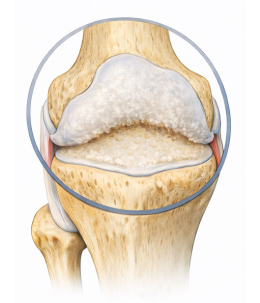

퇴행성관절염이란?

Degenerative arthritis퇴행성관절염은 연골이 반복적인 자극과 노화로 인해 손상되면서 염증과 통증을 유발하고,

결국 움직임에 제한을 가져오는 질환입니다.

다양한 요인으로 연골에 지속적인 자극이 가해지면서 관절을 보호하는 능력이 크게 감소하게 됩니다.

정상적인 모습

환자의 모습